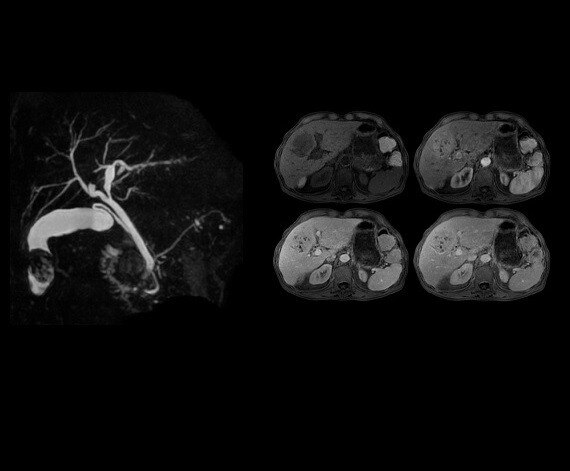

Auto Navigator is GE's solution to combat respiratory motion in abdominal imaging. This free-breathing approach is compatible with multiple pulse sequences including diffusion, PROPELLER MB, MRCP and dynamic T1 imaging.CVWorks

The four images demonstrate dynamic T1 imaging with PB Navigator, which enables the patient to breathe freely while capturing contrast in fast temporal phases. Whole spine evaluation can be obtained simply with routine T2 frFSE imaging.

3D MRCP